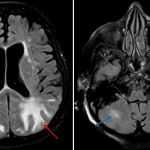

- Multifocal subcortical white matter hypoattenuation, most prominent in the parietal and occipital lobes as well as in the cerebellar hemispheres

- Small focus of hypoattenuation in the left thalamus

- Posterior reversible encephalopathy syndrome (PRES)

Posterior predominant white matter hypoattenuation involving the bilateral parieto-occipital regions and cerebellum in a pattern most suggestive of posterior reversible encephalopathy syndrome (PRES). Recommend brain MRI for further evaluation.

Lacunar infarct versus dilated perivascular space in the left thalamus.

No loss of gray-white differentiation to suggest associated ischemia, though MRI is more sensitive. No acute hemorrhage, mass effect, or hydrocephalus.